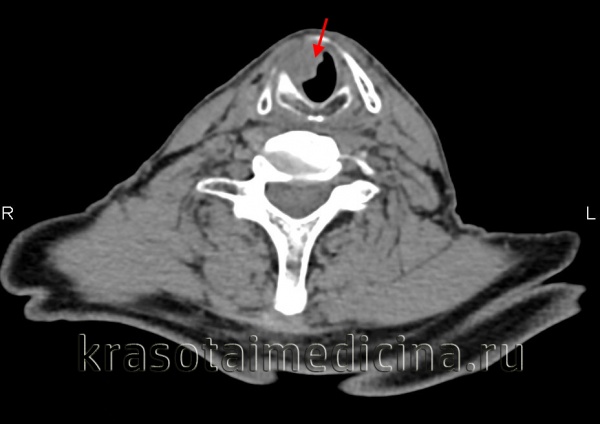

Определение распространенности опухоли уха проводится при помощи КТ черепа, КТ и МРТ головного мозга, ангиографии, фарингоскопии и других обследований.